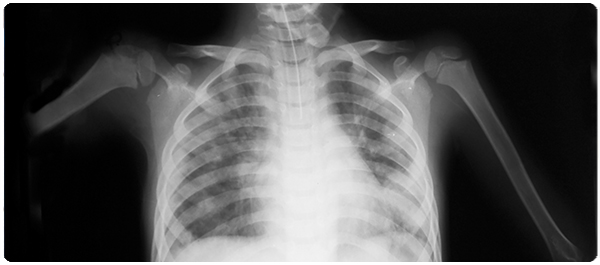

โรคปอดอักเสบ หรือ โรคปอดบวม (Pneumonia) เป็นโรคติดเชื้อในปอด ทำให้ปอดเต็มไปด้วยของเหลวหรือน้ำหนอง (Pus) ที่เป็นต้นเหตุให้เกิดอาการไอมีเสมหะหรือมีหนอง เป็นไข้ หนาวสั่น และหายใจลำบาก

- เกิดเฉพาะที่ส่วนหนึ่งของปอดหรือที่กลีบใดกลีบหนึ่งของปอด ที่เรียกว่า ปอดบวมเฉพาะกลีบหรือโลบาร์นิวโมเนีย (Lobar pneumonia)

- มีการแพร่กระจายไปทั่วปอดทั้งสองข้าง ที่เรียกว่า บรองโคนิวโมเนีย (Bronchial pneumonia / bronchopneumonia)